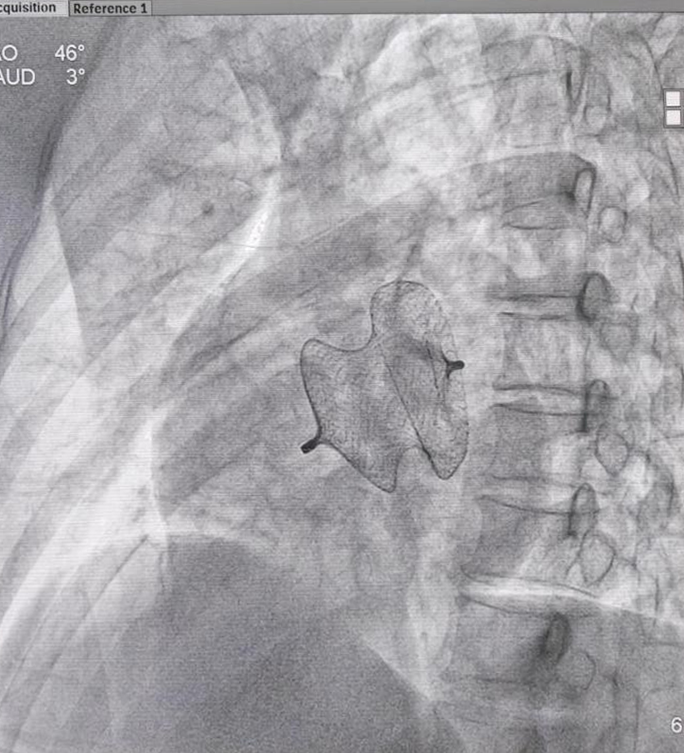

一名中年女性患者,因「间断心慌、气促、水肿 1 年加重 1 周,反复头晕」收治入院,诊断为先天性心脏病——房间隔缺损。经进一步详细检查心脏结构,确定了患者房缺最大直径约 30 mm,左向右分流。考虑到患者年龄,合并严重肺动脉高压等因素,经详细术前讨论认为患者可以采取经皮房间隔缺损封堵治疗方案。征得患者和家属同意后,7 月 26 日为患者施行介入手术。

该项新技术的突破,标志着西藏阜康医院心血管内科在结构性心脏病的介入治疗上迈出坚实的一步。